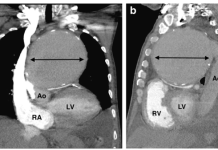

TÓM TẮT

Viêm động mạch chủ (Aortitis) là...